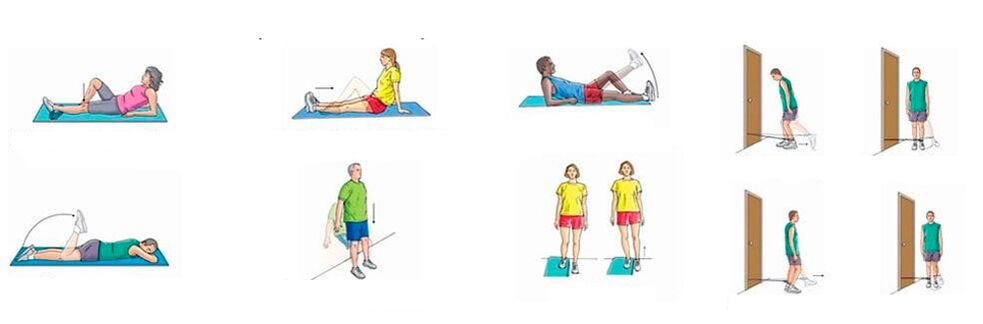

With chronic pain in the knee joints, when there is no significant inflammation, you can perform physical exercises that strengthen the muscle-ligament system, improve circulation and metabolism.Systematic training leads to a gradual decrease in pain, despite the fact that the legs are quite crunchy.

An approximate set of exercises for knee pain:

- Fixed knee.Lie on your back, bend one leg at the knee, raise it and keep it in that position for a minute;the other leg is immobile at this moment;straighten and lower your leg very slowly, rest for 10 seconds and repeat the exercise with the other leg;repeat 10 times;

- Double leg bend with knees close to face.Lie on your back, bend your legs at the hips and knees, attach the latter close to your face and hold for a minute.Then slowly straighten and lower your legs, rest for 10 seconds and repeat;do 5-6 approaches, gradually increasing the load.

Acute knee pain requires rest;any physical activity and training are contraindicated.

In the case of acute pain in the knee joint, accompanied by swelling and redness of the skin, general condition disorder, elevated temperature, you cannot move the leg, it must be kept at rest.And only after the inflammation begins to subside, you can move first to passive exercises (performed by an assistant), and then to active exercises (performed by the patient himself).